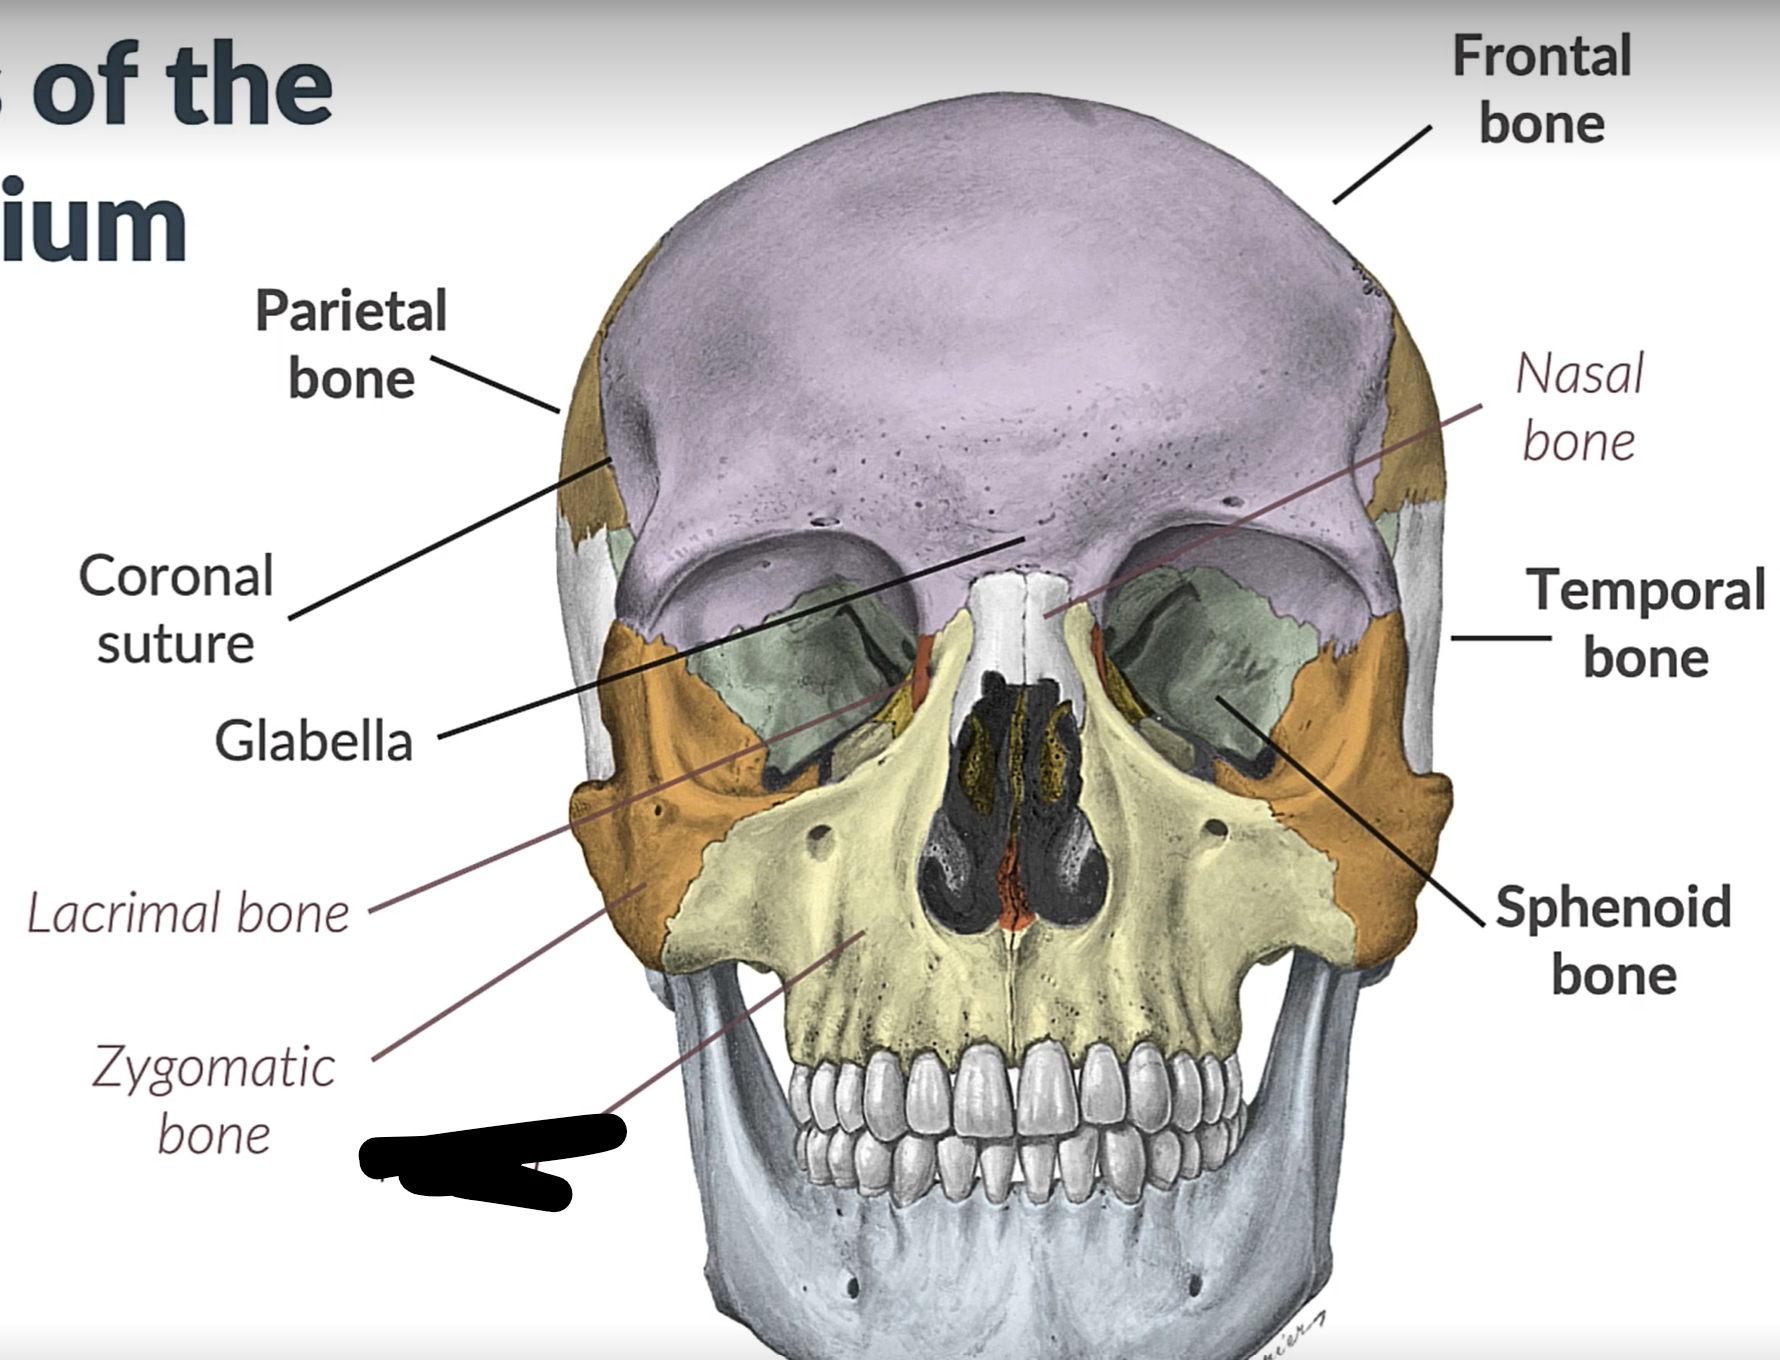

Parietal bone

Frontal bone

Temporal bone

Sphenoid bone

Zygomatic bone

Lacrimal bone

Coronal suture

Maxilla

Frontal bone

Coronal suture